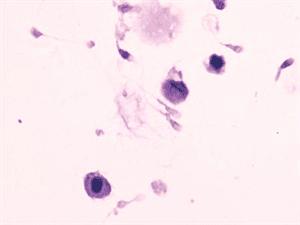

17世纪的法国哲学家有一句名言:“我思故我在”。可以看出,意识在很长时间里都是哲学讨论的话题。现代科学认为,意识是从大脑中数以亿计的神经元的协作中涌现出来的。但是这仍然太笼统了,具体来说,神经元是如何产生意识的?近年来,科学家已经找到了一些可以对这个最主观和最个人的事物进行客观研究的方法和工具,并且借助大脑损伤的病人,科学家得以一窥意识的奥秘。除了要弄清意识的具体运作方式,科学家还想知道一个更深层次问题的答案:它为什么存在,它是如何起源的?

上个世纪50年代,科学家发现大脑中的“海马区”在存储信息的过程中扮演着至关重要的角色——如果切除掉海马区,那么以前的记忆就会一同消失。但是海马区的神经细胞如何把信息固定下来?科学家发现一些分子参与到了记忆的形成。此外,神经细胞突触地形成也与记忆相关联。但是,科学家目前对于记忆的运作机制的了解还不够——而这一机制对于理解我们自身是非常重要的。